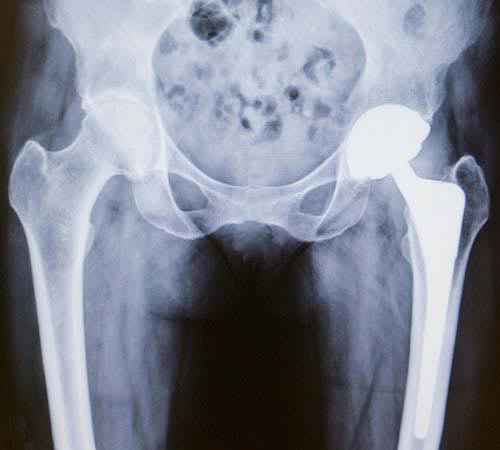

X-ray of a total hip replacement showing the ball, socket and stem implants

There are three separate implants: the stem, the ball and the socket.

- The stem, made of metal (usually titanium, cobalt-chrome or stainless steel) is inserted into your natural thighbone. For patients with poor bone quality (osteoporosis), the surgeon may elect to use bone cement to fix the stem to the bone. Otherwise, the bone of the femur grows onto the metal stem, when bone cement is not used.

- The ball is usually made of cobalt-chrome or ceramic and fits on top of the stem.

- The socket is usually a combination of a plastic liner and a porous titanium shell. The pelvic bone grows onto the titanium implant. Sometimes the surgeon elects to use screws through the titanium shell to further secure the implant to the pelvic bone.